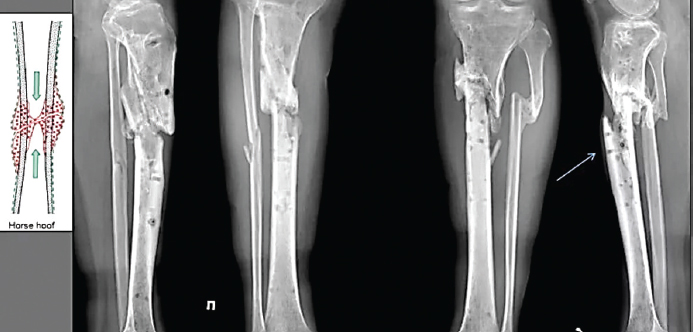

Хроническая форма гематогенного остеомиелита развивается как следствие острого гематогенного остеомиелита. При хроническом остеомиелите образуются абсцессы (гнойные скопления) костного мозга, происходит резорбция и секвестрация (отделение части кости) некротизированных участков. Вблизи очага нагноения выражено происходит резкое утолщение кости, её деформация образуются свищи, через которые выделяются небольшие костные секвестры (рис. 17).

Рис. 17. Хронический остеомиелит голени / Fig. 17. Chronic osteomyelitis of lower leg

Осложнения возможны в виде патологических переломов поражённой кости, образования ложных суставов, кровотечения из свищей, вторичного амилоидоза, иногда сепсиса, могут возникать опухоли. Прогноз благоприятный после хирургической санации очага гнойного воспаления.

Хронический остеомиелит огнестрельного происхождения также является осложнением острых форм болезни, которые приобретают характер «эпидемии» в период интенсивных военных действий (рис. 18).